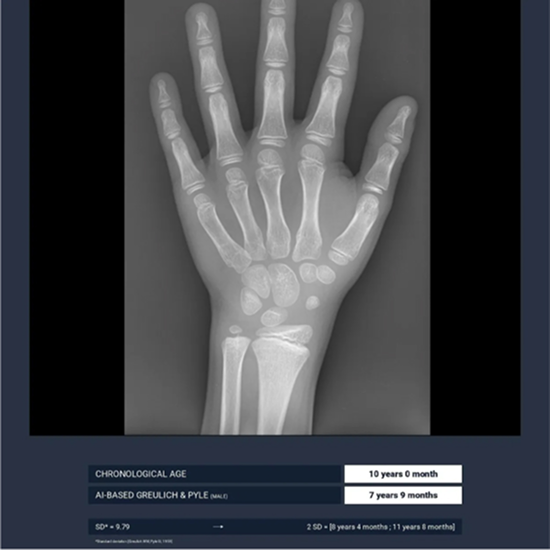

The AI-supported application BoneAge reduces both inter- and intra-variability.

Compared to the pediatric radiologist’s gold standard, the algorithm demonstrates utmost accuracy.

This is confirmed by Gleamers clinical study.